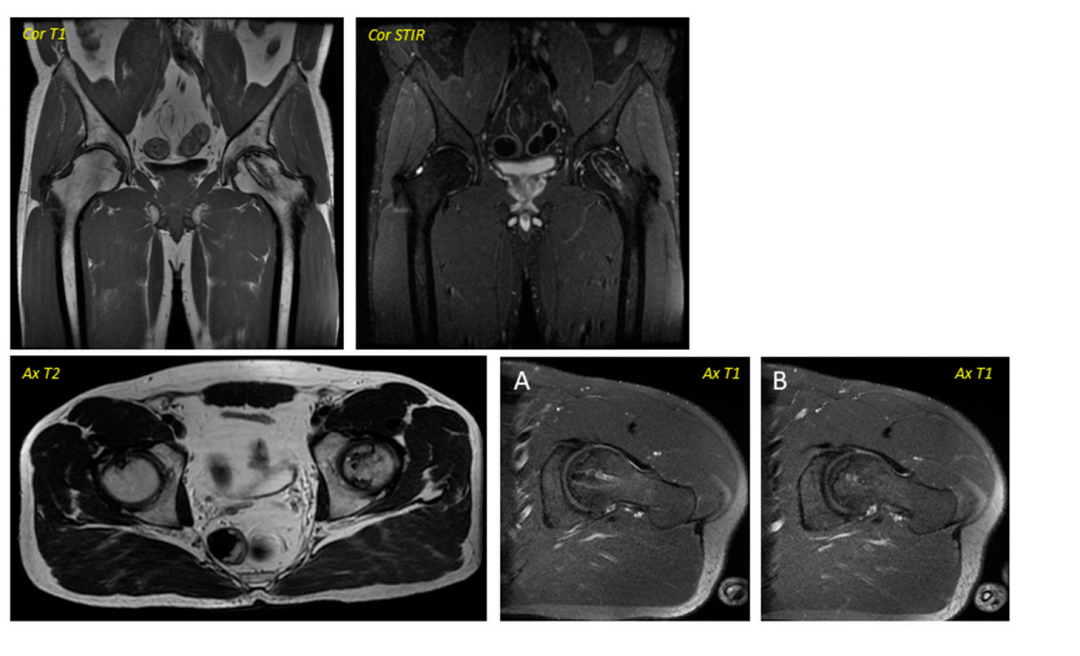

④影像学变化:在早期阶段变化并不明显,第6个月开始所有患者出现改变;62.5%的患者(n = 5)在手术后的一年内实现了影像学稳定(部分患者影像学图1、2)。

图1:对应于2013年12月执行的一名38岁男性术前图像